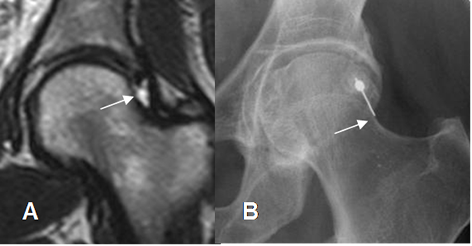

En la actualidad la ArtroRM es el gold estándar para determinar la lesión del labrum y cartílago articular. (4).

Para realizar la ArtroRM, se prefiere la guía fluoroscópica. Se utiliza un abordaje anterior, con leve rotación interna del muslo. Luego de comprobar la localización intra-articular, con una prueba de contraste yodado, se inyecta la mezcla de gadolinio y solución salina entre unión del cuello y la cabeza femoral, donde la capsula es mas amplia. (8). (Fig 24 y 25).

Fig 24.Técnica de ArtroRM.

A: RM coronal en T2. Lugar mas amplio de la cápsula articular, que se aprovecha para la punción.

B: Rx AP. Extremo de la aguja colocado en la unión entre el cuello y la cabeza femoral.